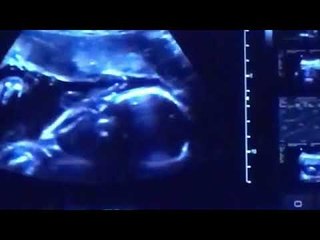

Bapa saudara ramal Kate dapat bayi perempuan

Uploaded: 2017-12-06

Duration: 01:35